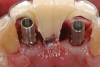

Preoperatively, 1 g of amoxicillin was administered. Using local anesthesia (lidocaine 1:100,000 epinephrine), extractions of teeth No. 23 to No. 26 were performed without raising a flap and with gentle luxation to preserve the remaining facial osseous plate. The sockets were curetted prior to implant placement. A vacuum-formed surgical guide, fabricated based on a diagnostic wax-up of the desired tooth positions for the subsequent fixed prosthesis, was used during implant placement. Osteotomies were performed at sites No. 23 and No. 26 and positioned toward the lingual aspects of the sockets (Figure 3A and Figure 3B). Two tapered implants (OsseoTite™ 313, BIOMET 3i™, Palm Beach Gardens, FL) measuring 3.25 mm x 13 mm were placed. Conical prosthetic abutments (3-mm height) were used to facilitate joining the two implants in a screw-retained fixed partial denture (Figure 4). A laboratory-processed acrylic-resin provisional restoration was altered to allow connection to the temporary cylinders. The provisional was placed into the vacuum-formed surgical guide that was now used to maintain the provisional in the correct 3-dimensional position (Figure 5) while being attached to the temporary cylinders with acrylic resin intraorally. Once a sufficient amount of acrylic resin was placed to secure the cylinders to the provisional, it was removed from the mouth and its contours were completed at the laboratory bench (Figure 6A). The two central incisor sockets were grafted with small-particle allograft material (Puros® Allograft, Zimmer Dental, Carlsbad, CA) to maintain gingival architecture beneath two ovate pontics (Figure 6B). The provisional restoration was inserted and the screws tightened to 20 Nt-cm of torque.

Figure 3a 3  Osteotomies prepared lingually.

Figure 3a

Figure 3  Placement of implants without flap elevation.

Figure 3